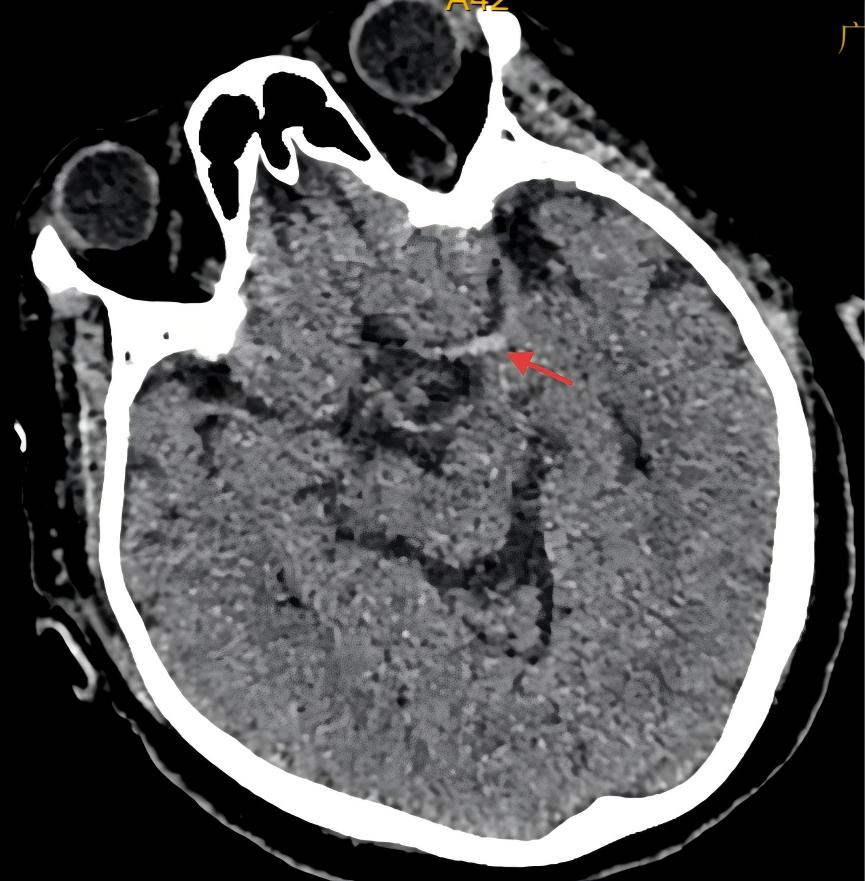

林奶奶到达急诊科时已处于昏睡状态,情况十分危急。急诊团队立即启动脑卒中绿色通道积极抢救,卒中团队医师熟练紧凑地询问病史、神经系统体格检查,快速完成头颅CT,CT结果提示“左侧大脑中动脉高密度影,考虑脑栓塞”。

头颅CT提示左侧大脑中动脉高密度影(红色箭头)